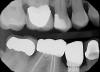

The presence of dark spaces, even from a cross-sectional photographic view, may indicate that an aftermarket part was used (Figure 13). Radiographically, everything should appear intimately tight against the implant interface (Figure 14). A visually absent intimate connection may indicate that the abutment/restoration and implants are incompatible (Figure 15).

Fig 14. Radiograph showing an authentic implant/abutment complex at tooth No. 4 and an incompatible implant/abutment complex at tooth No. 5, where the entire preload is on the screw.

Figure 14